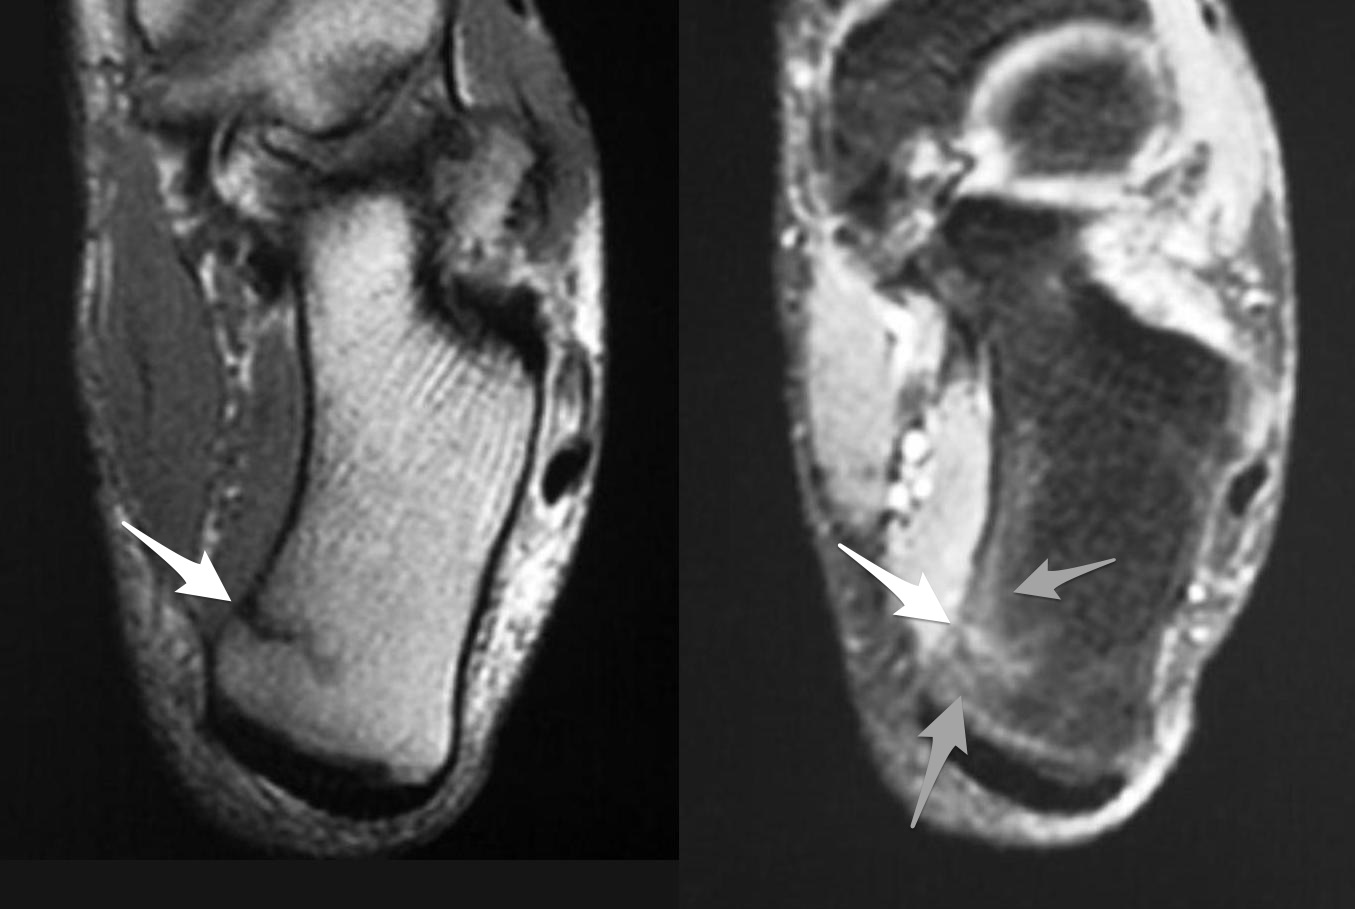

Gãy xương mệt mỏi

» Thông tin: Nữ giới – 23 tuổi.

» Lâm sàng: Đau bàn chân.

# Đường gãy xương + phù tủy xương.

Gãy xương bàn III

# Gãy xương bàn II